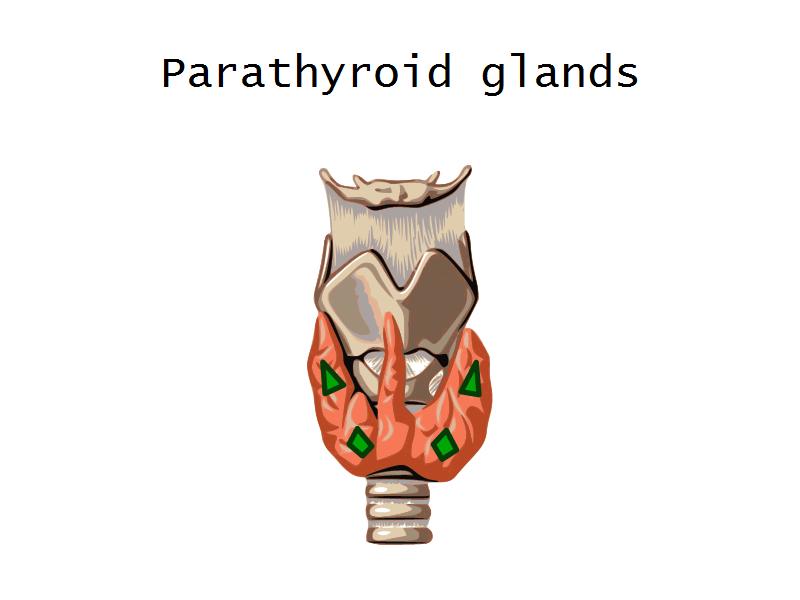

- Parathyroid glands

- G2: Parathyroid

- G2: Parathyroid = anterior neck behind the thyroid gland

- Slide 54: Parathyroid glands

Chief cells = majority

Oxyphil (acidophil) = single/groups